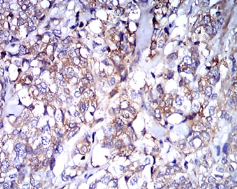

IHC    1/200 - 1/1000